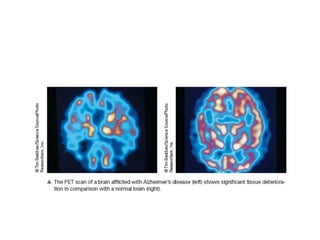

• #27 This shows the PET scan of a brain afflicted with Alzheimer’s disease (left) compared to a normal brain (right).